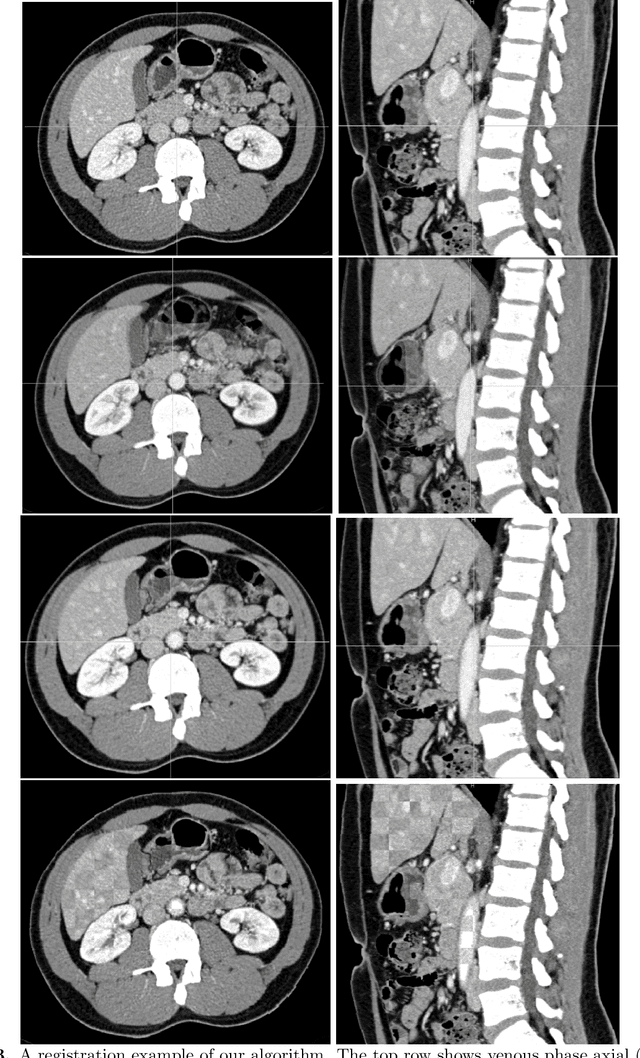

Abstract:Human body is a complex dynamic system composed of various sub-dynamic parts. Especially, thoracic and abdominal organs have complex internal shape variations with different frequencies by various reasons such as respiration with fast motion and peristalsis with slower motion. CT protocols for abdominal lesions are multi-phase scans for various tumor detection to use different vascular contrast, however, they are not aligned well enough to visually check the same area. In this paper, we propose a time-efficient and accurate deformable registration algorithm for multi-phase CT scans considering abdominal organ motions, which can be applied for differentiable or non-differentiable motions of abdominal organs. Experimental results shows the registration accuracy as 0.85 +/- 0.45mm (mean +/- STD) for pancreas within 1 minute for the whole abdominal region.